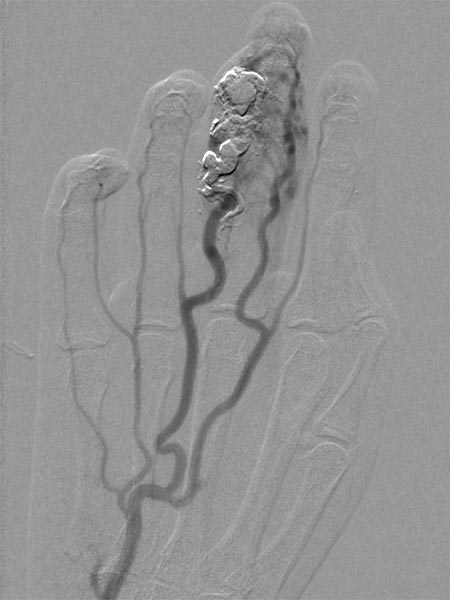

After incomplete transarterial embolization of the AVM 2 years ago, a recurrence of the AVM has appeared. During previous embolization only a part of the AVM was occluded, which actually increases the risk of recurrence. The old radiopaque embolic agent of the previous embolization can be seen centrally in the nidus.

The nidus of the AVM in a magnified target image of the D III in digital subtraction angiography shows significant increase in size compared to the old angiographies (not shown). DSA images after transarterial antegrade puncture of the brachial artery with hypervascularized AVM of the middle and distal phalanx.